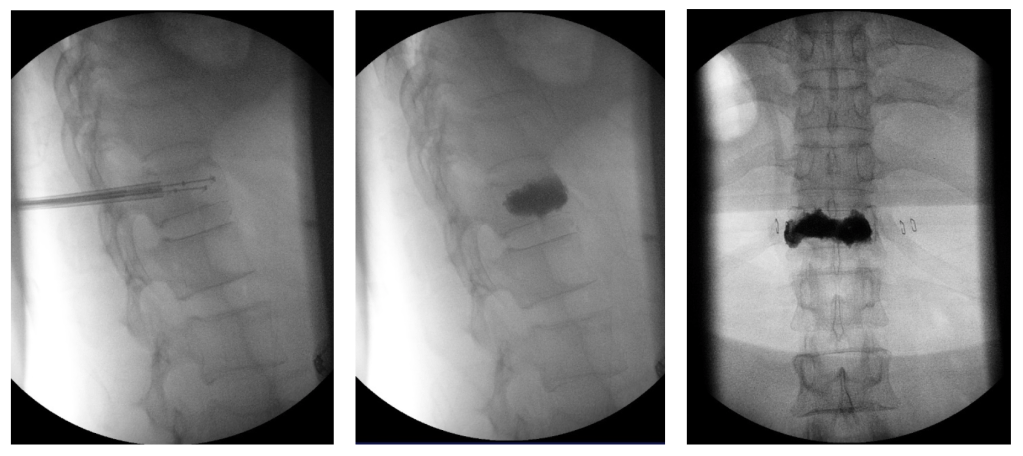

ในการฉีดซีเมนต์ยึดกระดูกสันหลัง (Vertebroplasty) ผู้ป่วยจะอยู่ในท่านอนคว่ำ บนเตียงผ่าตัด จากนั้นจึงเริ่มลงมีดในตำแหน่งที่จะปักเข็มประมาณ 2-3 มิลลิเมตร เมื่อปักเข็มเข้าไปในกระดูกสันหลังและยืนยันตำแหน่งโดยใช้เครื่องถ่ายรังสีเอ็กซ์ (X-ray/Fluoroscope) จะทำการฉีดสารทึบแสงทางเอ็กซเรย์เพื่อดูตำแหน่งที่จะฉีดซีเมนต์ว่าปลอดภัยหรือไม่ มีโอกาสที่ซีเมนต์จะรั่วออกมากดไขสันหลังหรือไม่ เมื่อมั่นใจว่าได้ตำแหน่งที่เหมาะสมแล้ว จะทำการฉีดซีเมนต์เข้าไปในกระดูกสันหลังเพื่อยึดกระดูกสันหลังที่แตก

ในขณะที่ฉีดซีเมนต์เข้ากระดูกสันหลัง แพทย์จะเห็นภาพในจอรับภาพของเครื่องถ่ายรังสีเอ็กซ์อยู่ตลอดเวลา หลังจากฉีดซีเมนต์แล้วจะให้ผู้ป่วยนอนหงายประมาณ 2-3 ชั่วโมง เพื่อให้ซีเมนต์แข็งตัว หลังจากนั้นผู้ป่วยจึงสามารถลุกนั่งหรือยืนได้

ตัวอย่างผู้ป่วยที่ได้รับการฉีดซีเมนต์ด้วยวิธียกถ่างกระดูกสันหลังที่แตกยุบด้วยบอลลูน

ทั้ง 2 ข้างก่อนฉีดซีเมนต์

ภาพเอ๊กซเรย์จากจอมอนิเตอร์ในห้องผ่าตัด แสดงภาพขณะฉีดซีเมนต์ โดยการยกถ่างกระดูกสันหลังด้วยการใช้บอลลูน (Balloon Kyphoplasty)